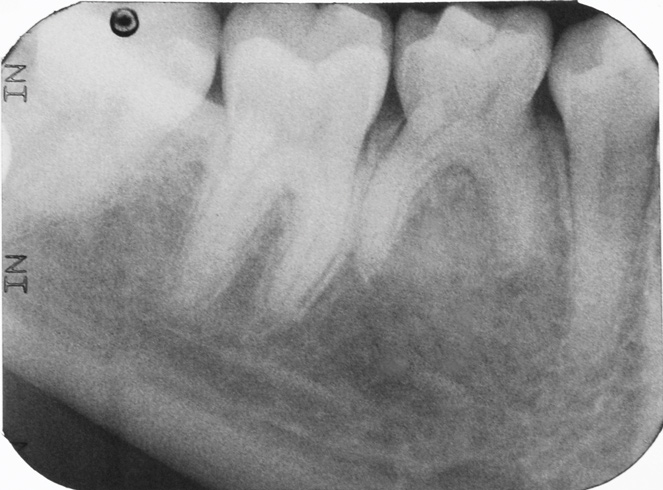

Fig 6. Three thin soft dental picks were used simultaneously for SDF proximal surface saturations in a teenaged patient (Fig 3). After 60 seconds, the treated regions were covered with 5% fluoride varnish (Fig 4). A comparison can be seen of pre-SDF-treatment bitewing films (Fig 5) and 8-month post-SDF bitewing films (Fig 6) for the patient shown in Fig 3 and Fig 4. Radiolucencies were similar or improved, except for contact of maxillary first and second molars.

Fig 3. Three thin soft dental picks were used simultaneously for SDF proximal surface saturations in a teenaged patient (Fig 3). After 60 seconds, the treated regions were covered with 5% fluoride varnish (Fig 4). A comparison can be seen of pre-SDF-treatment bitewing films (Fig 5) and 8-month post-SDF bitewing films (Fig 6) for the patient shown in Fig 3 and Fig 4. Radiolucencies were similar or improved, except for contact of maxillary first and second molars.

Fig 5. Three thin soft dental picks were used simultaneously for SDF proximal surface saturations in a teenaged patient (Fig 3). After 60 seconds, the treated regions were covered with 5% fluoride varnish (Fig 4). A comparison can be seen of pre-SDF-treatment bitewing films (Fig 5) and 8-month post-SDF bitewing films (Fig 6) for the patient shown in Fig 3 and Fig 4. Radiolucencies were similar or improved, except for contact of maxillary first and second molars.

Interproximal insertion of SDF is demonstrated in different patients in Figure 3 through Figure 11. Various diameters and brands of soft dental picks may be used depending on the closeness of the proximal surfaces and ease of insertion; for example, some picks are designed for use in wider spaces between teeth. This protocol also offers versatility. Figure 3, for example, shows the simultaneous use of three thin soft dental picks to saturate proximal surfaces with SDF in a teenaged patient; the treated regions were subsequently covered with fluoride varnish (Figure 4). This patient was initially treated in April 2019 (Figure 5), with an identical re-application 3 months later. As shown in Figure 6, the December 2019 bitewing film revealed good results with the possible exception of the contact regions of the maxillary first and second molars. New SDF application was completed in the December appointment.